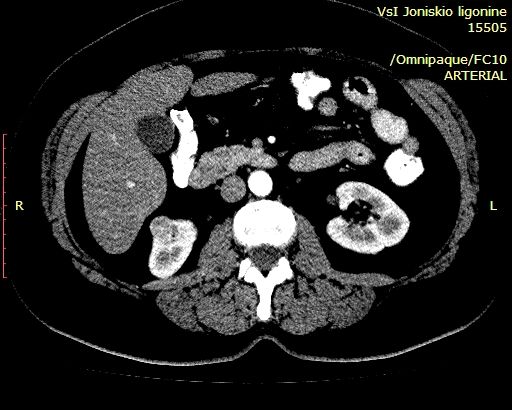

Немного похоже на AML, но неоднородное по структуре и с внутренним кровотоком, характеристики которого не в пользу RCC. Нет гипоэхогенного ободка, как при RCC.

Выполнена КТ с контрастированием.

Гистология - ангиомиолипома (выполнена резекция опухоли).